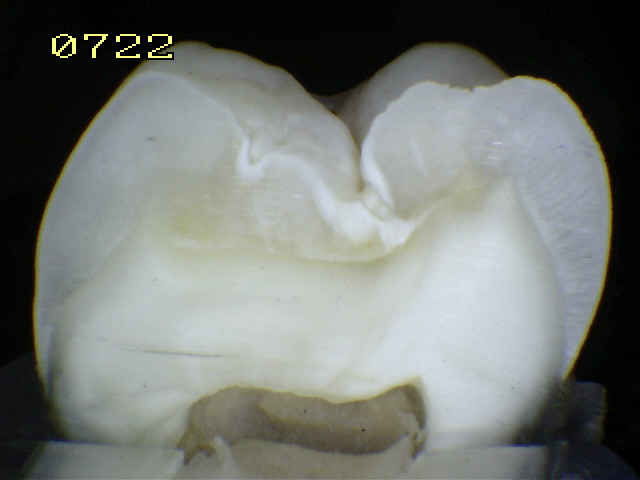

Espécimen Nº 28 |

| Corte sagital A:

Observe como el corte en la fosa presenta caries en dentina,

compatible con un código 2 histológico |

Corte sagital B: En la fisura es un

código 2 histológico |